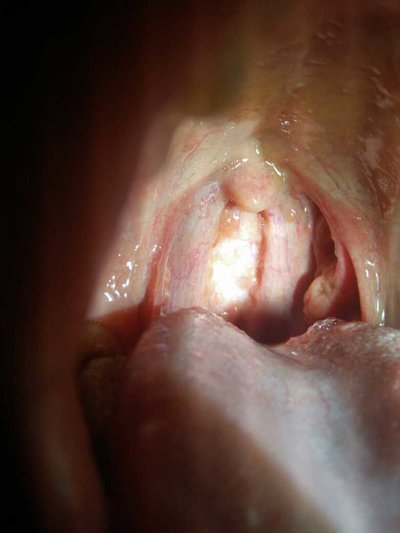

Sometimes, inflammation or infection in one aspect may lead to local pain or other complications. Therefore, effective treatment should be carried out. Acute pharyngitis is a common disease. Patients with acute pharyngitis may have infection in the pharyngeal mucosa and swelling and pain in the throat, It may also lead to hoarseness, so it is better to take early medication in order to avoid more serious symptoms and dysphagia. The symptom of acute laryngitis tells everybody now.

Many people with acute laryngitis may also lead to sore throat and hoarseness. Some people may have coarsening voice. Patients with acute laryngitis may have foreign body sensation in their throat. Generally speaking, it does not interfere with normal diet.

Acute pharyngitis patients will appear more obvious throat part of the production of mucus secretions, some patients may appear cough phenomenon, some people appear acute pharyngitis will cause more obvious cough phlegm phenomenon, the best in the early onset of drug treatment can relieve the throat pain.